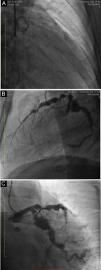

Single-plane fluoroscopy (Figure 1A) and coronary angiography showed a giant calcified aneurysm (73 mm×72 mm) of the mid-right coronary artery (RCA), and smaller aneurysms that were proximal and distal to the first. The proximal RCA was occluded by a thrombus (Figure 1B) so percutaneous revascularization could not be performed. The left coronary artery had multiple calcified aneurysms, and severe stenosis of the proximal anterior descending coronary artery (Figures 2A–C) was found. We performed ascending aortography, which was normal. These findings could be related to Kawasaki disease (KD). Despite good evolution following cardiogenic shock, the patient had upper gastrointestinal bleeding, a major and acute complication, which was fatal.